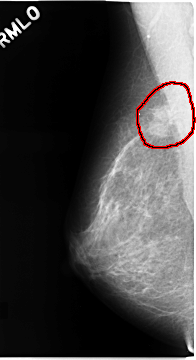

C_0110_1.LEFT_MLO

RIGHT_MLO LINES 4672 PIXELS_PER_LINE 2544 BITS_PER_PIXEL 12 RESOLUTION 50 OVERLAY

FILE: C_0110_1.RIGHT_MLO.OVERLAY

TOTAL_ABNORMALITIES 1

ABNORMALITY 1

LESION_TYPE MASS SHAPE IRREGULAR MARGINS SPICULATED

ASSESSMENT 5

SUBTLETY 5

PATHOLOGY MALIGNANT

TOTAL_OUTLINES 1

BOUNDARY